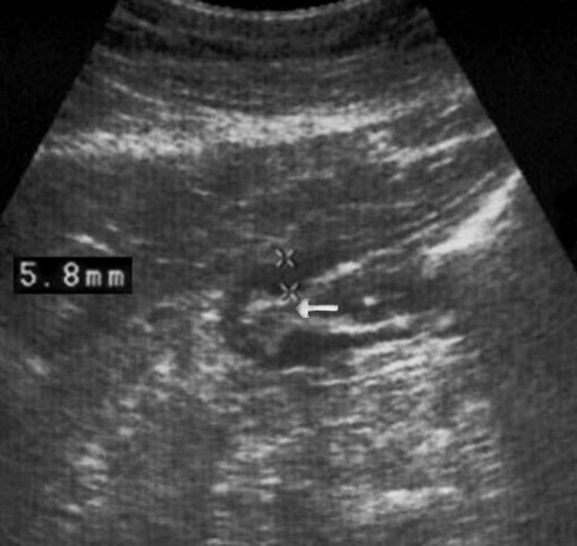

Distal gastric cancer was observed in 24 (39,3%) cases and contributed to the development of pyloric stenosis: in 6 (9,8%) cases it was compensated, in 18 (29,5%) – was sub compensated. The layers of the wall were not differentiated in all patients with sub compensated pyloric stenosis. In the case of compensated pyloric stenosis, the thickness of the affected area was 10,2±2,9mm, the length was 27,1±6,2mm, the diameter of the pylorus was 8,3±0,8mm (Figure 14). Among patients with sub compensated pyloric stenosis, the thickness of the stomach wall was 19,8±4,1mm, the length was 43,6±4,5mm, the pyloric diameter was 4,3±1,1mm (Figure 15).

Figure 14.Gastric carcinomas of diffuse infiltrative form in the atrium of T2 stage. Compensated pyloric stenos. On an empty stomach in the cavity of the stomach is determined an a small amount of fluid. The diameter of the pyloric canal more than 7 mm.